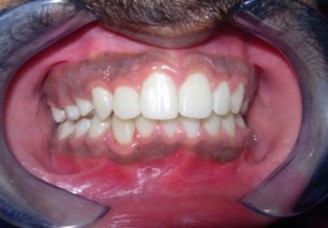

The soft tissue frontal and profile improved dramatically. (Figure 7a-b). The bilateral posterior crossbite was corrected. The severe increase in overjet of about 13mm was effectively reduced to 3mm and the severe deep bite was also corrected (Figure 7c,Figure 7d). Fixed maxillary and mandibular lingual retainers were given. (Figure 7e, Figure 7f). Post orthodontic treatment, normal root inclinations of the teeth and normal alveolar bone levels was observed. (Figure 8).

Figure 7c.Post-treatment intra-oral-Frontal

Figure 7d.Post treatment intra-oral – Right

The end of treatment result showed a good improvement in the transverse, anteroposterior, and vertical dimensions with markedly improved dentofacial esthetics.